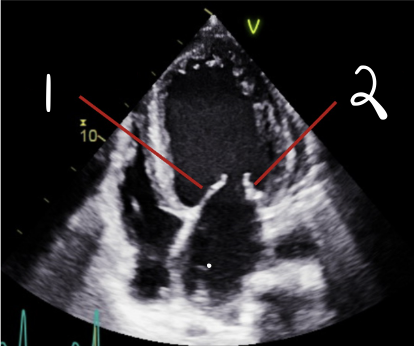

This is 4CH, What is 1?

Anterior

This is 4CH, What is 2?

Posterior